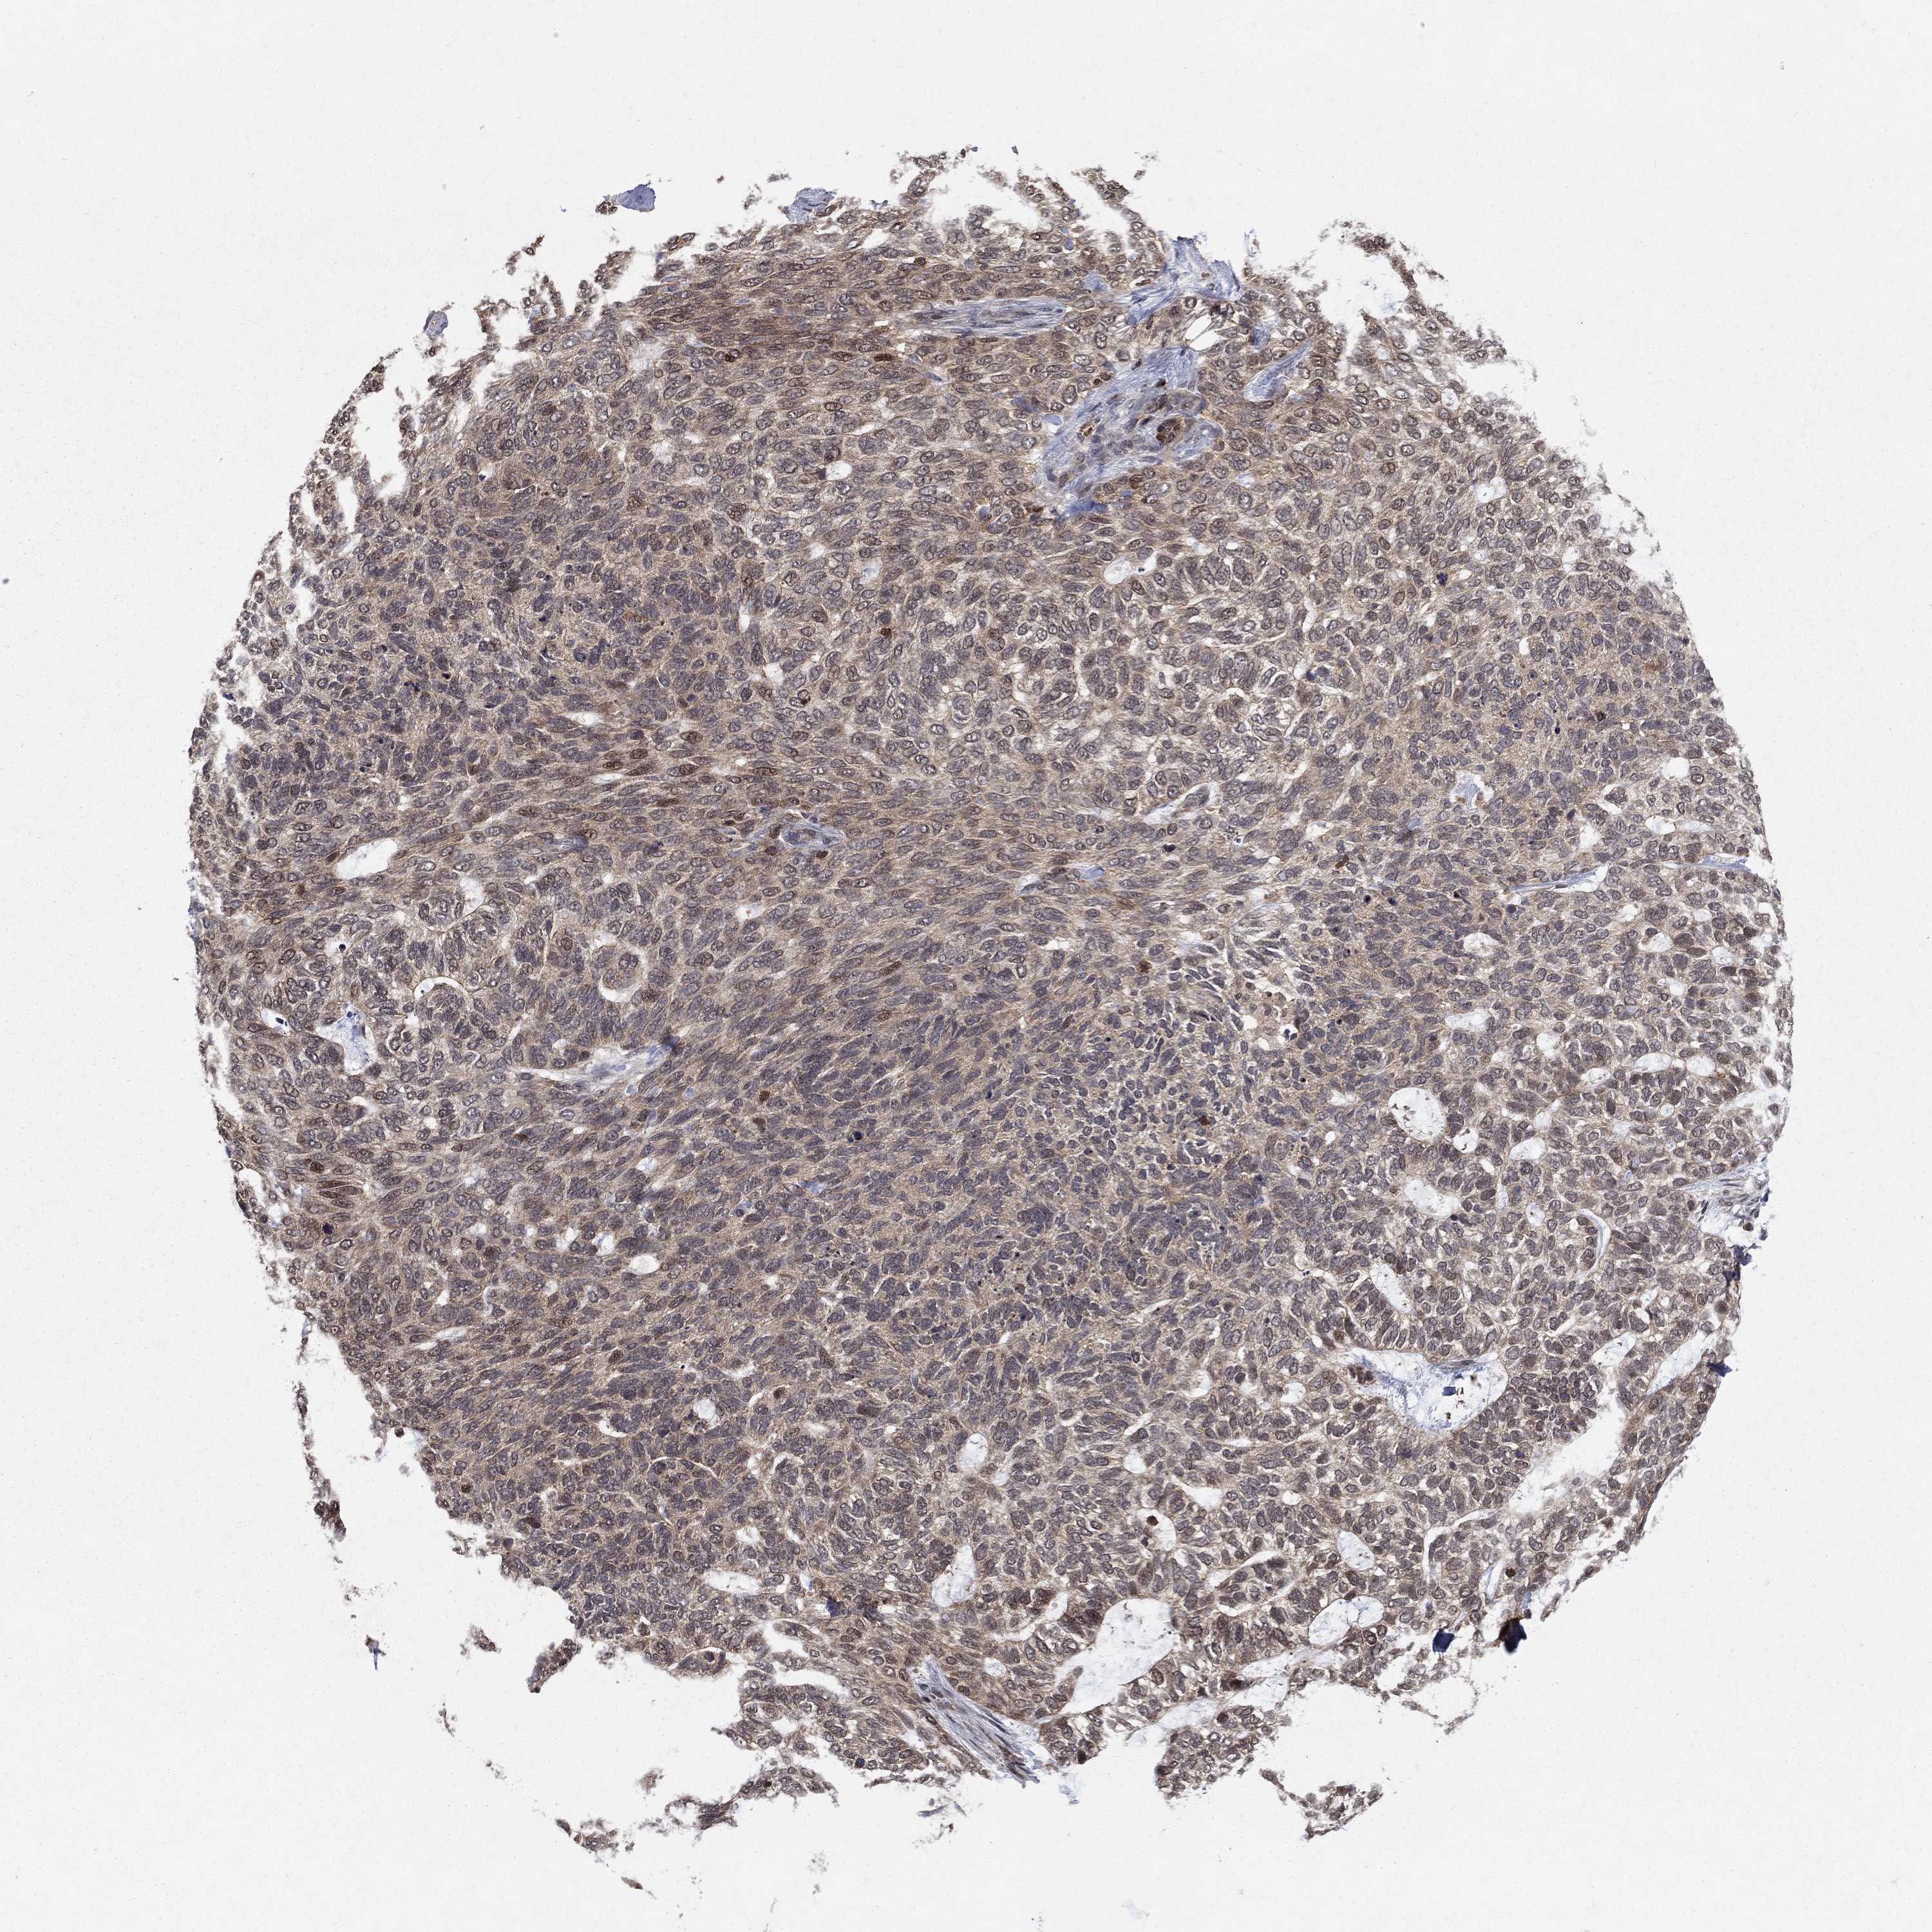

CANCER SKIN CANCER Show tissue menu

Basal cell and squamous cell cancer

SKIN CANCER - Protein expressioni

A mouse-over function shows sample information and annotation data. Click on an image to view it in a full screen mode. Samples can be filtered based on level of antibody staining by selecting one or several of the following categories: high, medium, low and not detected. The assay and annotation is described here.

Antibody stainingi

Antibody staining in the annotated cell types in the current human tissue is reported as not detected, low, medium, or high, based on conventional immunohistochemistry profiling in selected tissues. This score is based on the combination of the staining intensity and fraction of stained cells.

Each image is clickable and will lead to virtual microscopy that enables deeper exploration of all samples and also displays staining intensity scores, fraction scores and subcellular localization as well as patient and tissue information for each sample.

Antibody HPA051937

Staining

High

Medium

Low

Not detected

Intensity

Strong

Moderate

Weak

Negative

Quantity

>75%

75%-25%

<25%

None

Location

Nuclear

Cytoplasmic/membranous

Cytoplasmic/membranous,nuclear

Basal cell carcinoma

Squamous cell carcinoma, NOS